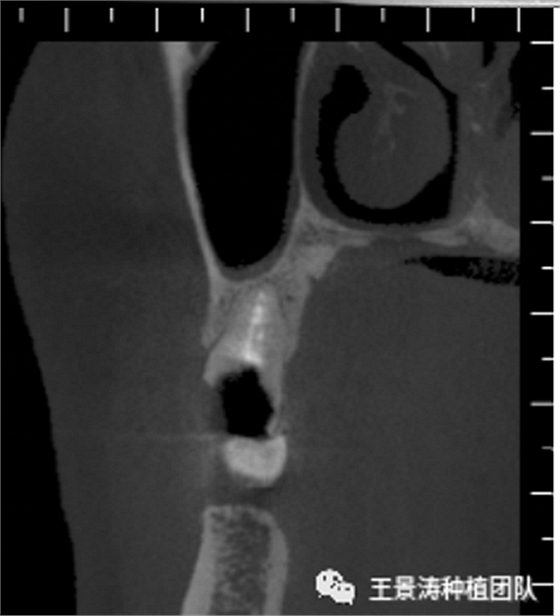

其次初期穩(wěn)定性的獲得,前牙美學(xué)區(qū)種植體的初期穩(wěn)定性主要是依靠腭舌側(cè)骨板及基底骨來獲得的。后牙區(qū)的穩(wěn)定性主要依靠多根牙的牙槽間隔及根尖到重要解剖位置的高度的骨質(zhì)獲得(主要是竇嵴距和管嵴矩的高度,還要參考植入種植體的長度),因此術(shù)前仔細(xì)測量牙槽間隔與根尖至重要解剖結(jié)構(gòu)的高度是后牙即刻種植的關(guān)鍵因素之一。

下述病例則是15區(qū)域的即刻種植,15因牙冠折斷于齦下,無法樁核冠修復(fù),則考慮種植修復(fù)。但拍攝CBCT后發(fā)現(xiàn)根尖距上頜竇底距離較短。患者為年輕女性,無全身系統(tǒng)疾病且可利用上頜竇底與根尖皮質(zhì)骨雙側(cè)皮質(zhì)骨固位,且此位置可通過頰側(cè)軟組織減張技術(shù)獲得嚴(yán)密封閉牙槽窩。因其根尖距上頜竇距離較低,遂拔除15后行上頜竇內(nèi)提升,埋入式種植,最終修復(fù)的完成。

左側(cè)下頜第二磨牙及右側(cè)下頜第一磨牙同時(shí)即刻種植病例?;颊吣贻p女性,無系統(tǒng)性疾病。37及46殘冠及殘根,且46劈裂,無法冠修復(fù),必須拔除。37根尖慢性炎癥,大量肉芽組織存在,46根分叉較高,根分叉骨質(zhì)尚可。CBCT示:根尖骨質(zhì)至下牙槽神經(jīng)管距離可滿足種植體的初期穩(wěn)定性,遂考慮即刻種植,并在種植體周邊填入骨粉并覆蓋骨膜,雙側(cè)的種植體初期穩(wěn)定性相差無幾,但考慮到37根尖慢性炎癥較大,遂給予埋入式種植。